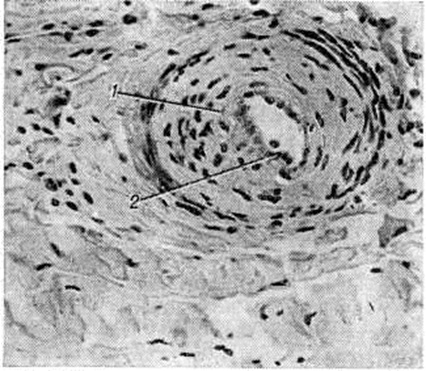

При активном течении патологический процесса васкулиты артериол и мелких артерий имеют пролиферативный характер с циркулярным разрастанием внутренней оболочки (рисунок 2). При электронной микроскопии в капиллярах поражённых тканей обнаруживается вакуолизация и деструкция эндотелия, а также многослойная базальная мембрана. По данным К луга (Н. Кlug) с соавторами (1977) и другие, при иммунофлюоресцентном исследовании материала, полученного при биопсии почек, мышц и кожи в стенках мелких артерий и капилляров, а также под сарколеммой мышечных волокон обнаружены депозиты IgM и комплемента.

Рис. 2.

Микропрепарат синовиальной оболочки коленного сустава при системной склеродермии: 1 — хронический продуктивный васкулит, 2 — пролиферация внутренней оболочки сосуда; окраска гематоксилин-эозином; ×200.